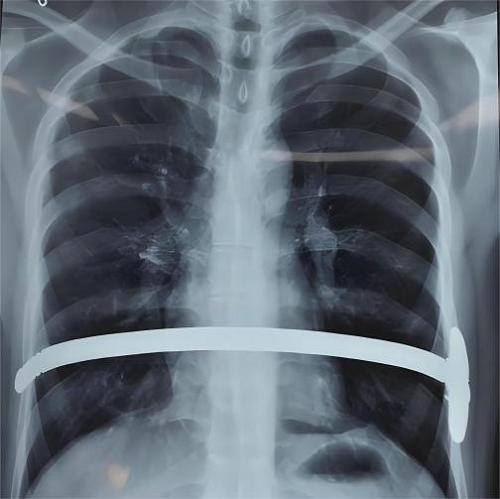

微创漏斗胸矫形术是在胸腔镜辅助下,将术前特制的Nuss钢板术中经规划的肋间,于胸骨后心包前置放在合适位置,进行钢板翻转,将胸骨抬举达到矫形的目的。矫形效果立竿见影。通常仅需双侧腋下两个小切口即可完成手术。术后要注意避免弯腰等不当动作,注意有无钢板移位的问题。对于无特殊情况的接受手术的患者一般术后2-4年拆除钢板。同时要重视术后心理辅导、康复训练及呼吸锻炼等,有助于畸形的矫正及心肺功能的康复。

钢板翻转矫形